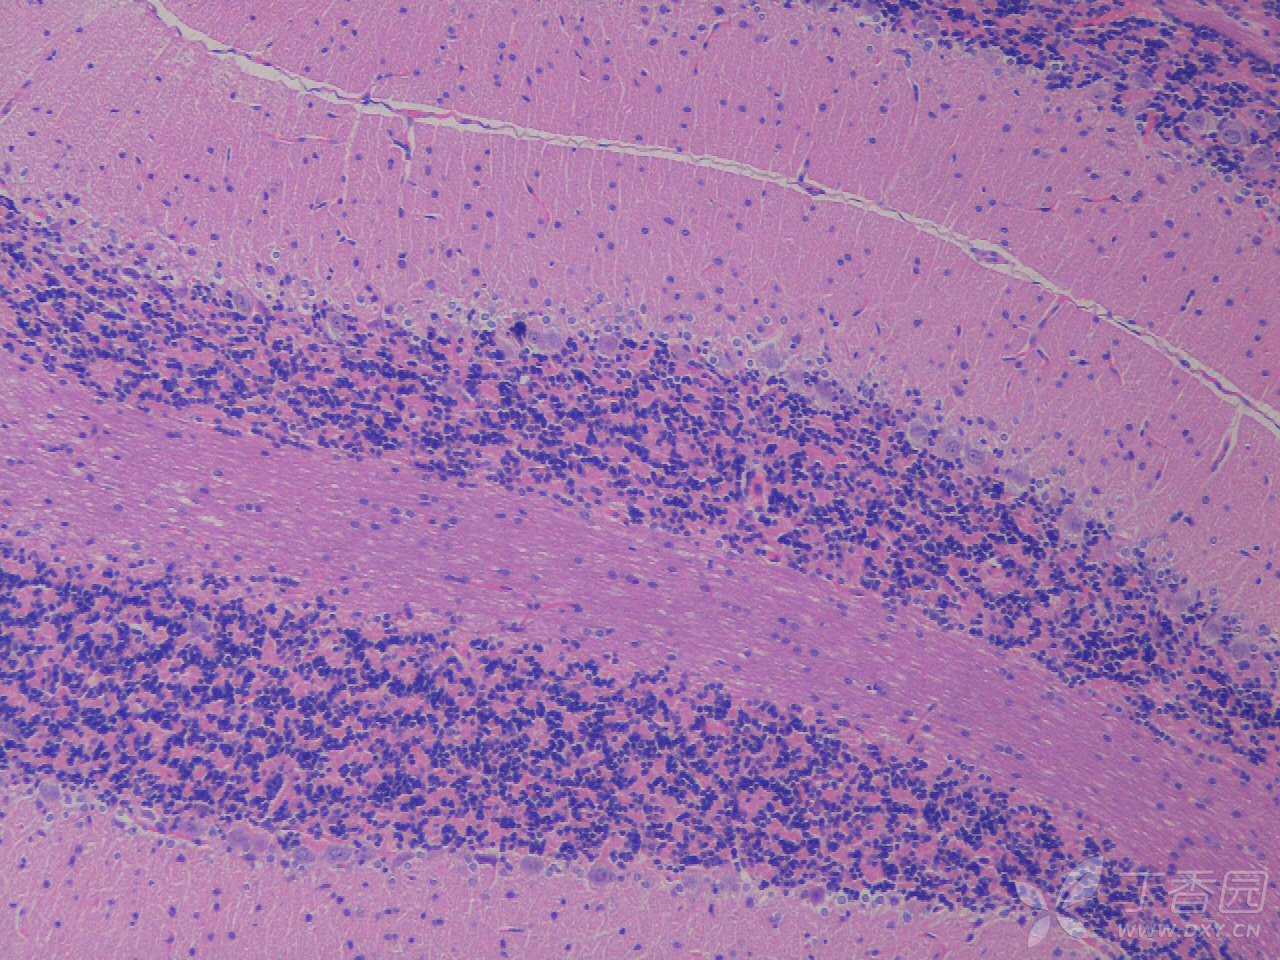

sd大鼠皮层及海马he染色及尼氏染色 神经元存活个数

图片尺寸1280x960